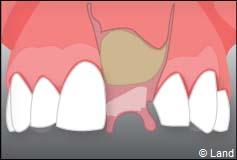

Le chirurgien-dentiste après une anesthésie locale pratique une incision, puis il décolle la gencive pour accéder à l’os alvéolaire.

Ensuite il prépare l’emplacement de l’implant dans l’os en passant plusieurs forets de diamètre croissant. Le forage de l’os se fait à vitesse maîtrisée et lente sous irrigation, pour respecter la structure osseuse et éviter tout échauffement de celle-ci. Le praticien arrête lorsqu’il a obtenu un puits d’un diamètre très légèrement inférieur à l’implant à poser.

L’implant est placé dans l’os le plus souvent par vissage et doit avoir une liaison forte avec l’os. Le praticien replace alors la gencive et pose des points de suture.

Il faut attendre après la pose de l’implant, l’ostéo-intégration, qui peut durer plusieurs mois. L’implant va se souder complètement avec l’os et contrairement à la dent naturelle, il n’y a pas de souplesse ou de mobilité physiologique dues au ligament alvéolo-dentaire.

À l’issue de sa mise en place chirurgicale, une bague de cicatrisation en titane peut être directement vissée sur l’implant. Ainsi une seconde chirurgie ne sera pas nécessaire pour découvrir l’implant.